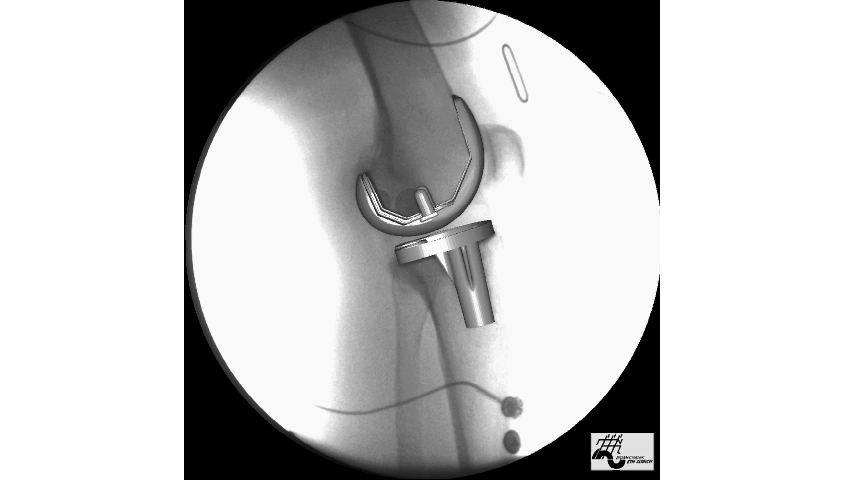

- traitement chirurgicalDans le passé, pour les patients souffrant d'une arthrose avancée plus sévère, nous procédions généralement à une intervention chirurgicale.Remplacement total de la surface du genou (hanche)En d'autres termes, la surface cartilagineuse usée est remplacée par une surface métallique, ce qui est similaire au processus de remplacement d'une prothèse dentaire par un appareil dentaire, et la surface cartilagineuse usée est remplacée par une surface métallique. Cette procédure est relativement plus invasive et certains patients ont tendance à avoir une usure plus importante du cartilage d'un côté de l'articulation, par exemple, le côté médial ou latéral est très usé, il est donc très pénible de devoir remplacer la partie la moins usée par une prothèse totale du genou. Par conséquent, de nos jours, nous préconisons également des traitements épargnant le genou, qui peuvent être effectués par ostéotomie et traitement orthopédique, ou par un remplacement d'un seul compartiment, afin d'essayer d'aider les patients les plus sévères à résoudre leurs problèmes. Le problème peut être résolu par l'ostéotomie et le traitement orthopédique, ou par le remplacement d'un seul compartiment. Bien entendu, le remplacement total de l'articulation est nécessaire pour les patients souffrant d'une arthrose avancée et particulièrement grave.

C'est avant tout pour lesUne petite introduction à la thérapie par étapes pour les patients souffrant d'arthroseNous devons souvent prendre d'abord des mesures simples et moins coûteuses, puis choisir des mesures relativement plus traumatisantes pour aider les patients à contrôler leurs symptômes, et s'ils ne trouvent toujours pas de soulagement, il se peut qu'ils doivent finalement subir une opération chirurgicale pour les aider à résoudre leurs problèmes.

Il est important que les patients souffrant d'arthrose comprennent que la maladie peut être complètement guérie si les symptômes du patient atteignent un stade avancé, ce qui signifie que l'arthroplastie peut aider le patient à résoudre complètement le problème.

Mais après tout, cette mesure comporte un certain risque, et le coût et le traumatisme de l'opération sont relativement élevés, de sorte que de nombreux patients ne choisissent pas cette mesure thérapeutique.